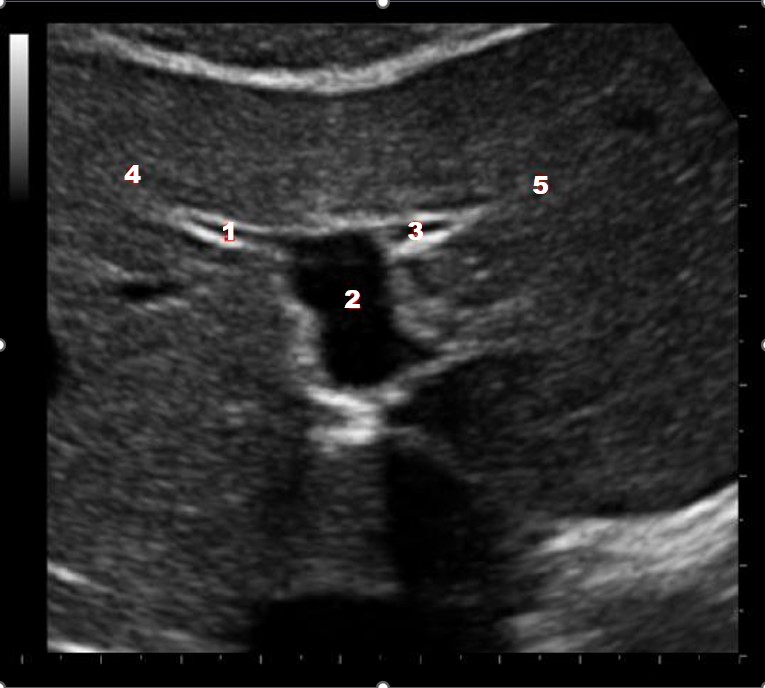

Which of the following structures is labeled number #1?

Left hepatic vein

Which of the following structures is labeled #2?

Middle hepatic vein

Which of the following structures is labeled #3?

IVC

Which of the following structures is labeled #4?

Right hepatic vein

Which structure/vessel is indicated by #5?

Lateral left lobe